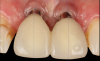

Fig 15. Clinical comparison of the volumetric gain obtained with the intervention, frontal views. Fig 15: Frontal view at baseline. Fig 16: Frontal view at 1-year post-treatment.

Figure 15

Fig 16. Clinical comparison of the volumetric gain obtained with the intervention, frontal views. Fig 15: Frontal view at baseline. Fig 16: Frontal view at 1-year post-treatment.

Figure 16